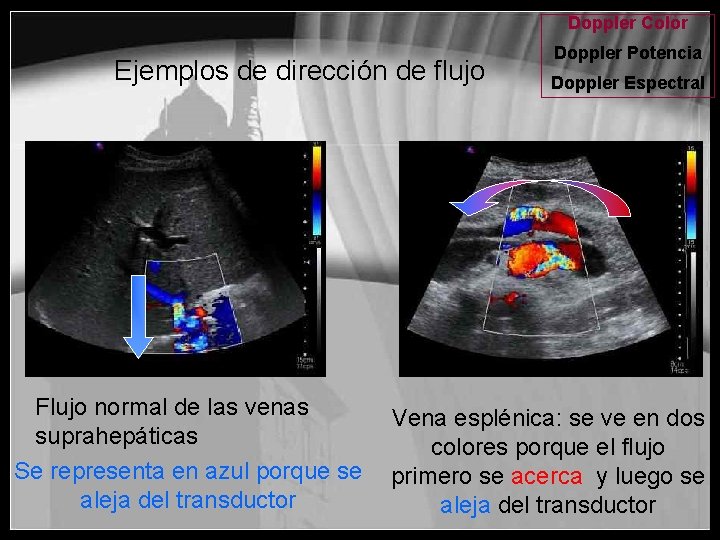

Doppler Color Ejemplos de dirección de flujo Flujo normal de las venas suprahepáticas Se representa en azul porque se aleja del transductor Doppler Potencia Doppler Espectral Vena esplénica: se ve en dos colores porque el flujo primero se acerca y luego se aleja del transductor